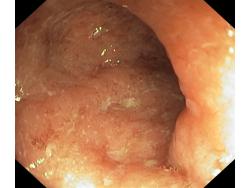

Zapalenie wrzodziejące...

Zapalenie wrzodziejące jelita grubego